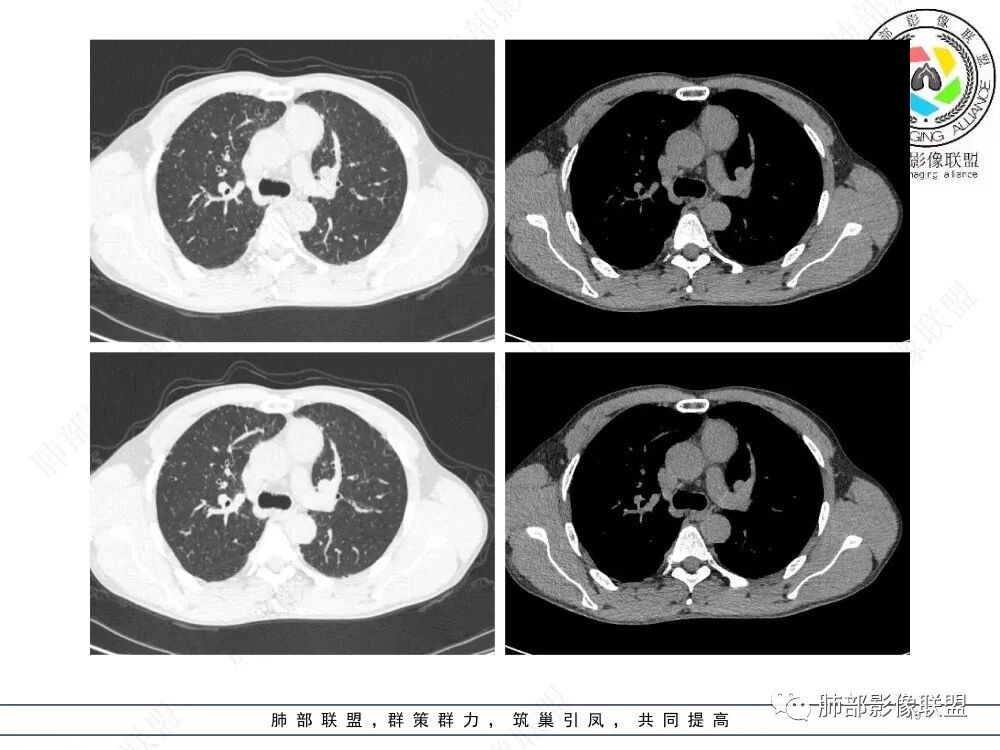

1、临床特点:47岁男性,咳嗽咳痰1年余。实验室检查无特殊。

2、影像特点:前纵隔偏左侧软组织影,密度相对均匀,未见明显包膜钙化及实质内钙化,局部边缘浅分叶,周围脂肪间隙密度增高、浑浊,未见侵犯大血管、未见纵隔内淋巴结转移、未见侵犯心包内结构、未见胸膜转移结节、未见肿块沿着纵隔胸膜蔓延,未见胸腔积液。增强后动脉期不均匀强化,未见明显纤维分隔。

3、 病 例 小 结:40岁以上,前纵隔偏侧性生长的肿块,常规考虑胸腺瘤。难点就在于胸腺瘤的分型。但是对于前纵隔占位影像诊断的关键在于区分胸腺囊肿、胸腺瘤、胸腺癌及其他恶性肿瘤。至于胸腺瘤,主要在于判断有无侵袭性。